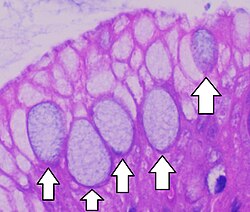

Adipose loose connective tissue

Matrix but very sparse. Closely packed fat cells have nucleus pushed to the side by large fat droplets. Functions to reserve fuel, insulate heat loss, and support organs. Found under skin, around kidneys and eyeballs, and within breasts

<p>Matrix but very sparse. Closely packed fat cells have nucleus pushed to the side by large fat droplets. Functions to reserve fuel, insulate heat loss, and support organs. Found under skin, around kidneys and eyeballs, and within breasts</p>